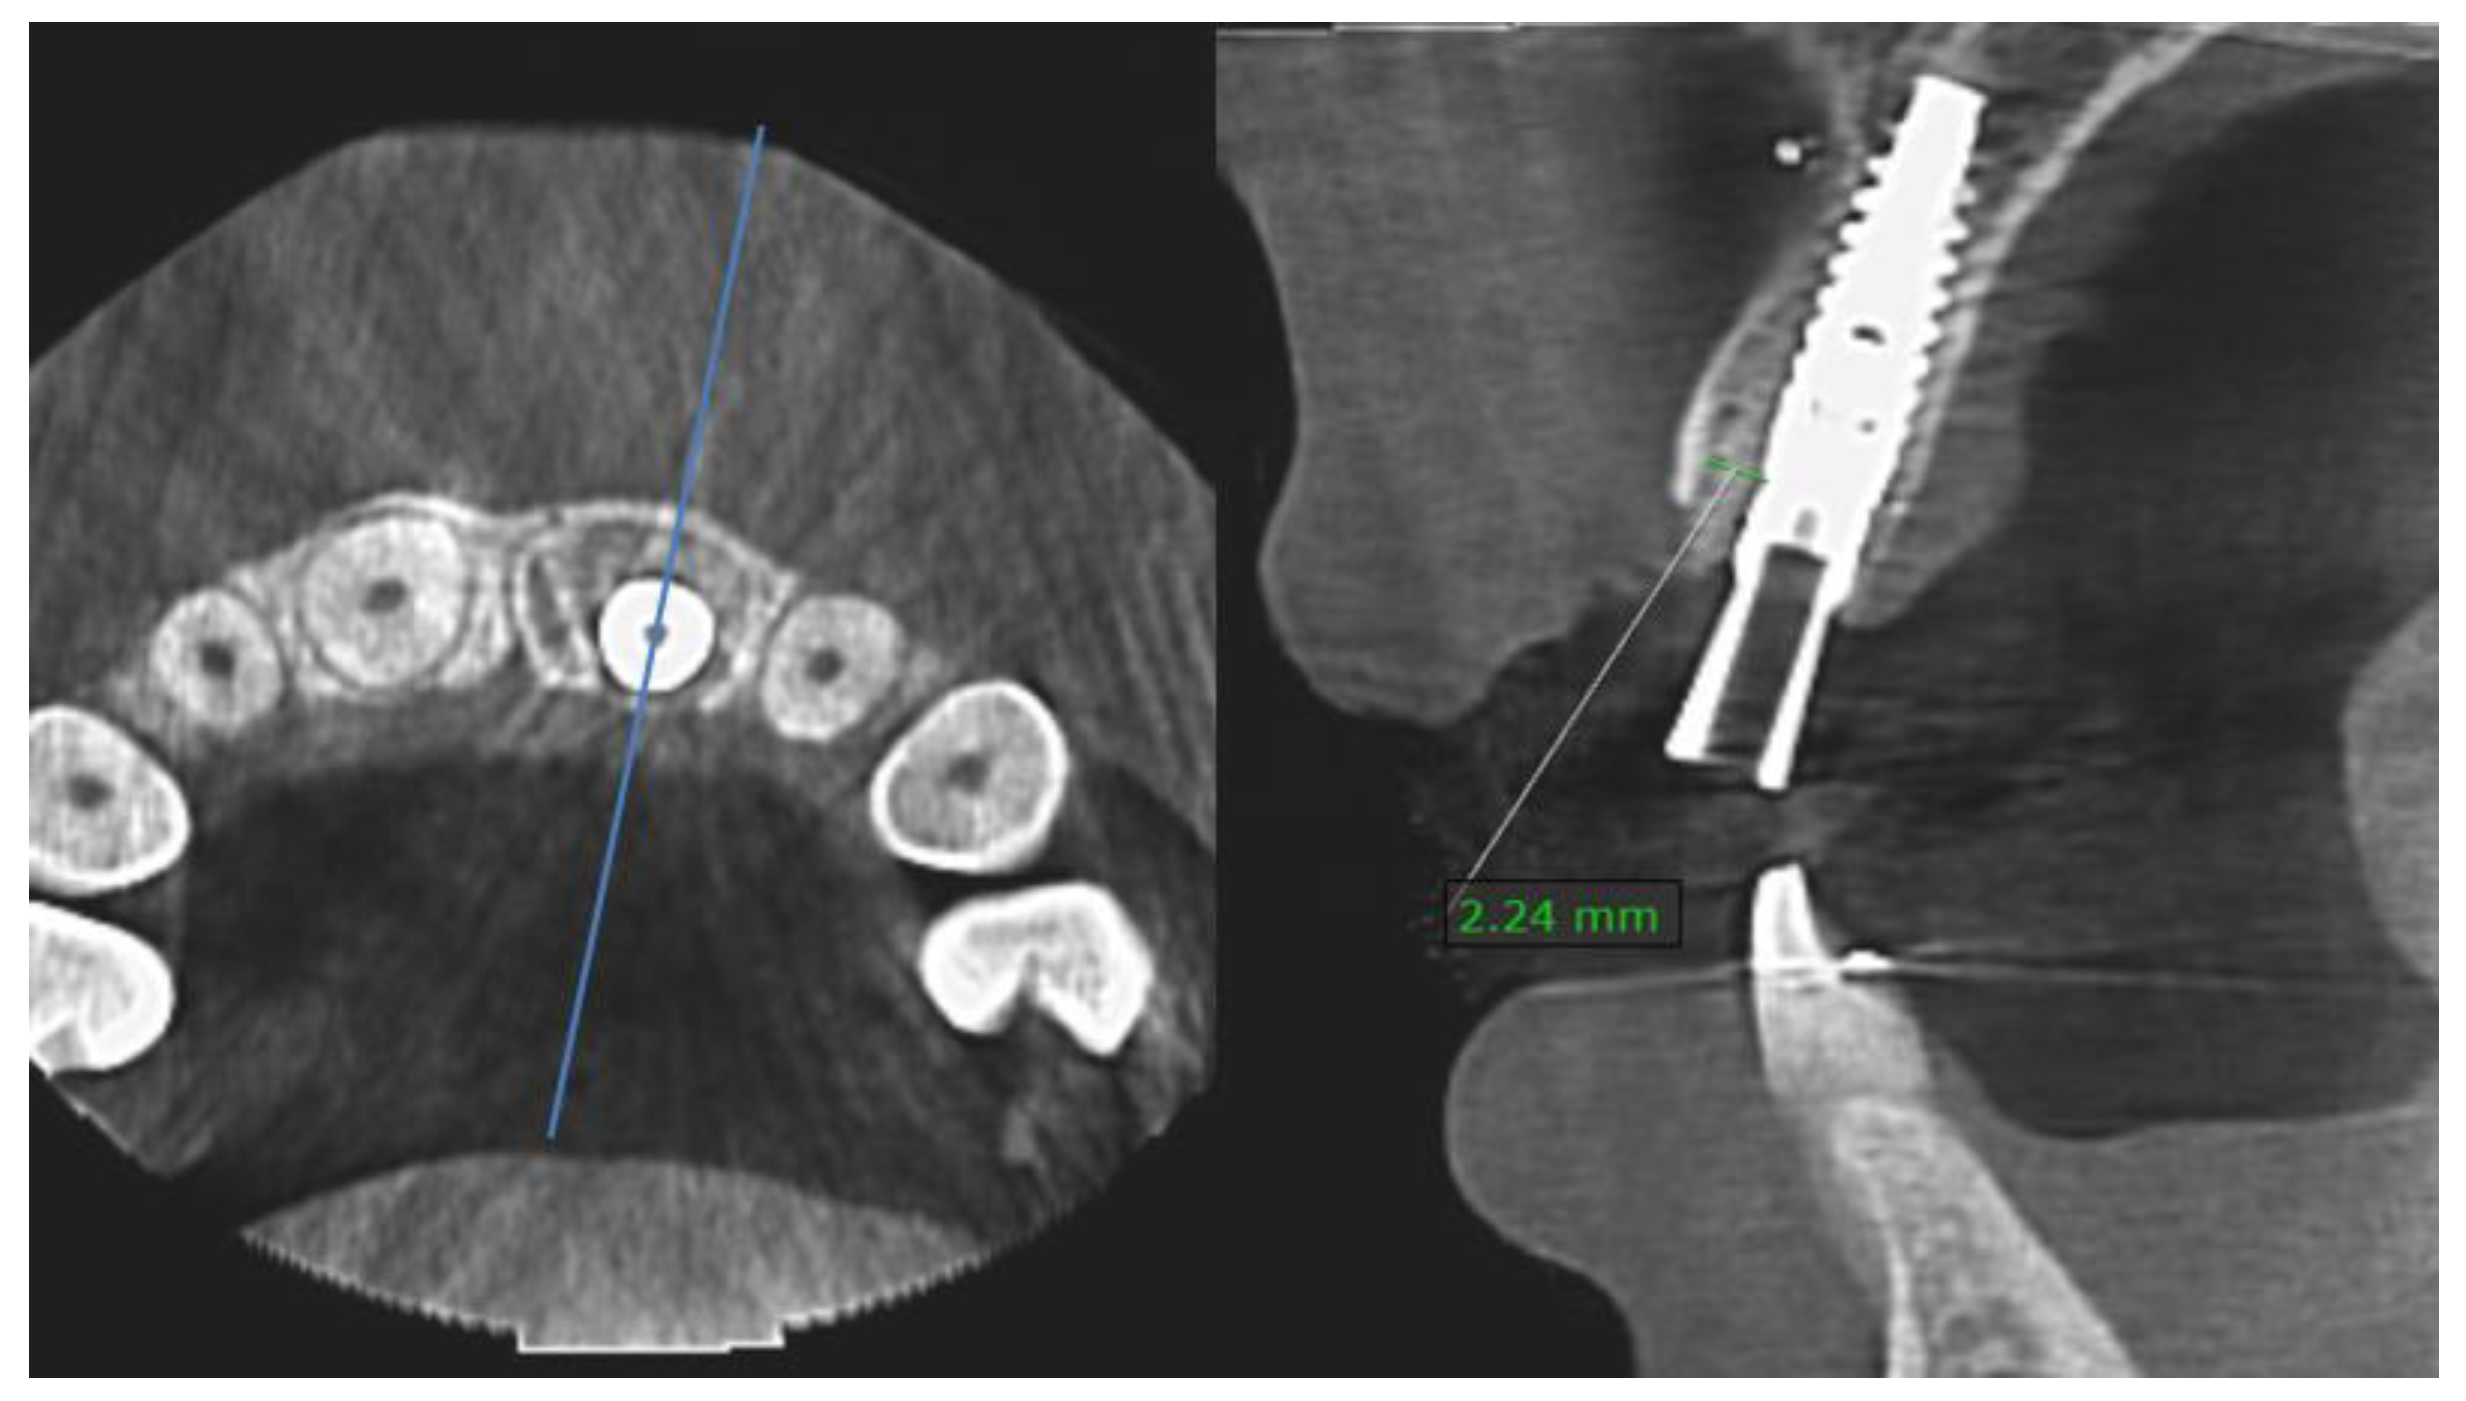

3.4. Bone Gap Measurements

3.5. Patient Satisfaction

- Staas, T.A.; Groenendijk, E.; Bronkhorst, E.; Verhamme, L.; Raghoebar, G.M.; Meijer, G.J. Does initial buccal crest thickness affect final buccal crest thickness after flapless immediate implant placement and provisionalization: A prospective cone beam computed tomogram cohort study. Clin. Implant. Dent. Relat. Res. 2022, 24, 24–33. [Google Scholar] [CrossRef]